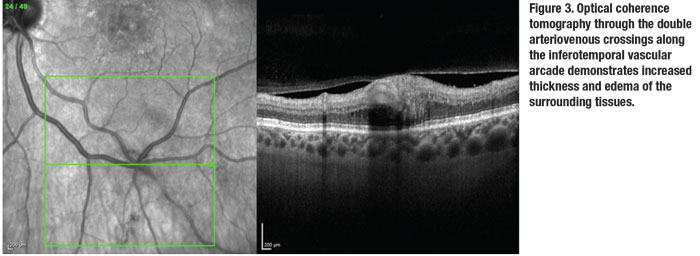

Additionally, given the pattern of intraretinal hemorrhages and delayed return in an isolated venous tributary, we diagnosed an incidental retinal vein tributary, or “twig,” occlusion. Interestingly, the juncture of the venous occlusion seemed to include not one but two arteriovenous (AV) crossings given its location at the branch point of both the arteries and the veins. We also obtained OCT through the AV crossings (Figure 3).

Like other types of vein occlusions, the mechanism of a twig occlusion is thought to be disruption of normal endothelium and laminar blood flow. Most pathology occurs at AV crossings, where thick, rigid-walled arteries compress the more flexible thin-walled vein neighbors. This compression or obstruction, or both, leads to disruption in normal laminar blood flow, leading to thrombus formation.3

In this patient with double AV crossings, development of a “twig” RVO provides circumstantial support for the presumed mechanism of injury. Given its stability and lack of other symptoms, we didn’t pursue further workup. A confounding point is that the patient continued treatment for her nAMD, and a lack of complications from the vein occlusion could be attributed to her ongoing anti-VEGF injections. RS